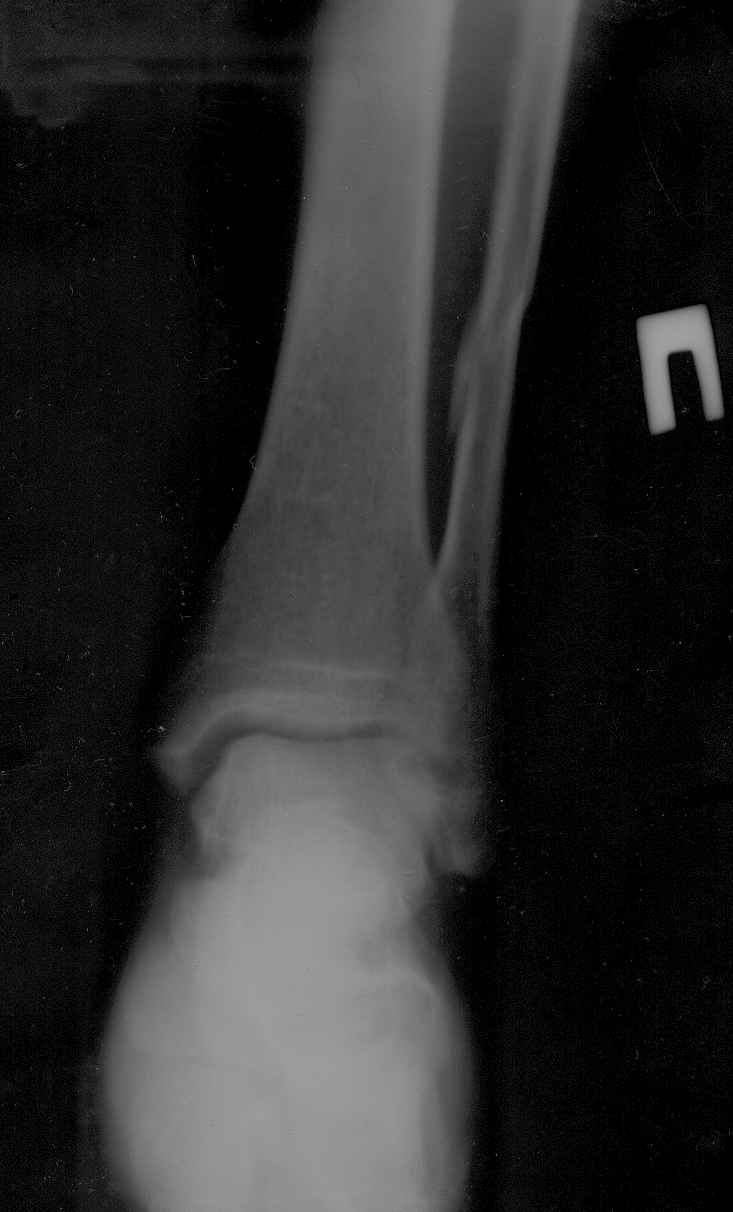

У пациента возраст 58лет закрытый перелом н/лодыжки почти без

смещения и н/3 малоберцовой кости со смещением правой голени.

Из сопутствующих-рассеяный склероз, ибс, гипертоническая болезнь.

ro-снимки прилагаются.подскажите оптимальный метод лечения